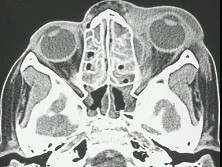

辅助检查中最有意义的发现是(如图)()